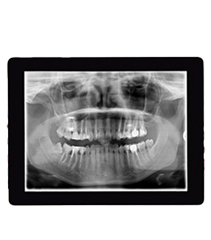

Digital X-Rays

When it comes to identifying dental issues early, digital X-rays are one of the most valuable tools we use. Unlike traditional X-rays, which require film development and produce higher radiation exposure, our digital system captures crystal-clear images instantly with significantly lower radiation—up to 90% less.

These high-resolution images allow us to detect cavities, bone loss, infections, impacted teeth, and other hidden issues before they become major problems. Because the images are immediately available, we can explain your diagnosis on the spot, answer your questions, and start building your treatment plan during the same visit.

It’s all part of our commitment to safe, proactive care that keeps you informed and in control of your oral health.